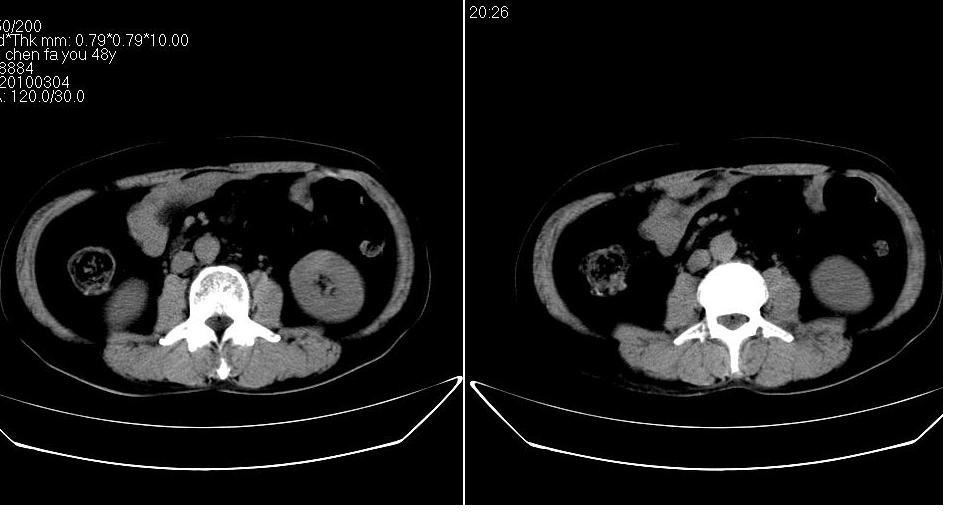

男 48岁,09年8月份在上级医院确诊胰头癌,准备在我院化疗。

胰头体积增大内见低密度影考虑为占位,肿瘤性病变可能性大。

胰头体积增大,外形不规则,密度欠均,支持胰头癌可能性大。